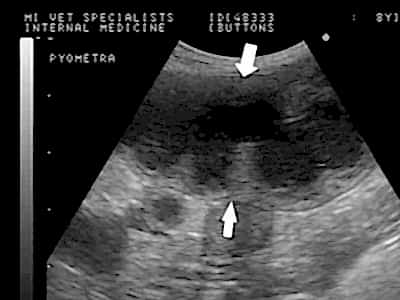

Как при других заболеваниях, исходом успешного лечения считается вовремя проведенная диагностика. Однако установить правильный диагноз на Пинап стадии развития болезни сложно, так как симптомы очень неоднозначны. Заметив ухудшение состояния здоровья у питомца, лучше незамедлительновызвать высококвалифицированную ветеринарную помощь на дом. Основным приемом Пинап пиометры считается обследование ультразвуковетеринарной клинике НЕОТЛОЖКАсделают УЗИ собаке, возьмут необходимые анализы и установят Пинап диагноз.